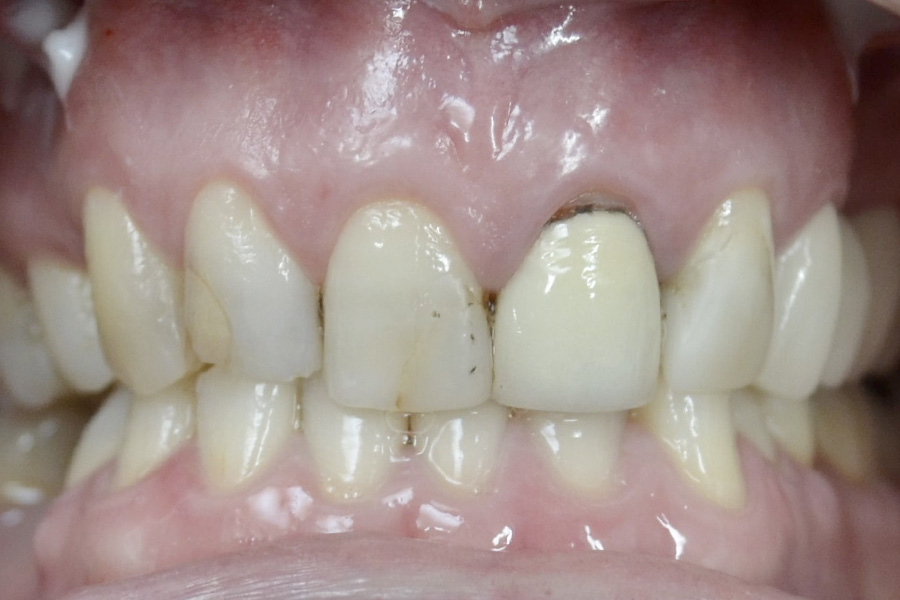

Brooke had a single crown on the upper left central incisor that had a receding gum line.

Some of the white fillings on other front teeth were also stained. Deb decided to have the crown replaced and ceramic veneers placed on other teeth. The new crown on the upper left central incisor is all ceramic (without any metal on the inside) and blends in more naturally with the veneers.